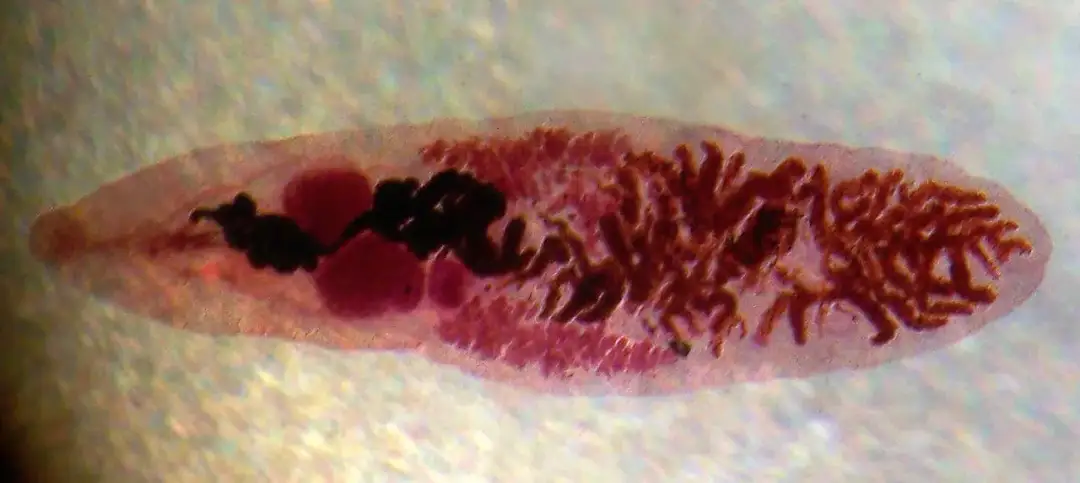

Odkryj, jakie badania na robaki pomogą Ci wykryć pasożyty jelitowe. Poznaj skuteczne metody diagnostyczne, od tradycyjnych po nowoczesne, i dowiedz się, kiedy warto je wykonać. Zadbaj o swoje zdrowie już dziś!

Odkryj metody wykrywania pasożytów we krwi. Dowiedz się, jakie badania krwi na pasożyty są najskuteczniejsze, jak się do nich przygotować i co oznaczają wyniki. Chroń swoje zdrowie już dziś!